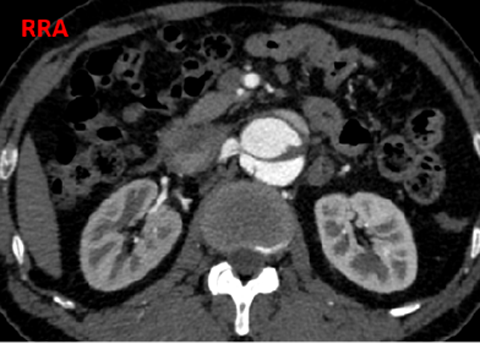

夹层近端封闭良好。夹层动脉瘤累及整个内脏区动脉,腹腔干、肠系膜上动脉假腔供血,腹腔干开口重度狭窄;右肾动脉真假腔供血,以假腔为主;左肾动脉真腔供血。肾下腹主动脉段无裂口,右侧髂外动脉存在裂口。

CT影像